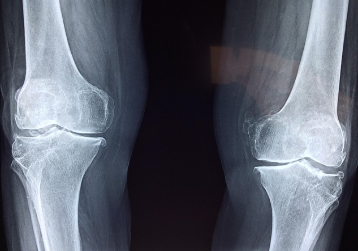

오랜 시간 앉아서 일하거나, 반복적인 동작을 자주 해야 하는 업무 환경, 운동 부족, 잘못된 자세 등은 관절에 무리를 주는 주요 원인입니다. 특히 무릎, 손목, 어깨, 허리 등 주요 관절에 부담이 누적되면 통증과 염증이 발생하고, 이로 인해 일상생활에 불편을 겪는 경우가 많습니다.

글루코사민은 관절 연골을 구성하는 기본적인 물질 중 하나로, 인체 내에서도 자연스럽게 생성되는 성분입니다. 하지만 나이가 들수록 그 생성량은 점차 줄어들며, 이로 인해 연골이 점차 마모되고 관절 간 마찰이 심해져 통증이나 염증으로 이어지는 경우가 많습니다. 따라서 글루코사민을 외부에서 보충해주는 것은 관절 건강 유지에 있어 매우 중요한 부분입니다.

글루코사민은 손상된 연골을 복구하고 새로운 연골 세포 생성을 촉진하는 역할을 합니다. 특히 무릎 관절과 같은 하중이 많이 실리는 관절 부위에 효과가 크며, 이미 관절염이 진행된 경우에도 통증 완화에 긍정적인 영향을 미치는 것으로 알려져 있습니다. 다수의 임상 연구에서 글루코사민이 관절염 환자의 통증을 감소시키고, 관절의 운동 범위를 개선하는 데 도움이 된다고 보고하고 있습니다.

또한 글루코사민은 관절액, 즉 윤활액의 생성을 촉진하여 관절 내 움직임을 부드럽게 유지하는 데 중요한 역할을 합니다. 윤활액은 마치 기계에 윤활유를 바르는 것과 같은 역할을 하며, 연골 사이의 마찰을 줄이고 충격을 흡수하는 기능을 합니다. 글루코사민이 충분히 공급되면 관절에서 나는 뻣뻣함이나 뻐근함이 완화되고, 움직일 때 느껴지는 저항감도 줄어들게 됩니다.